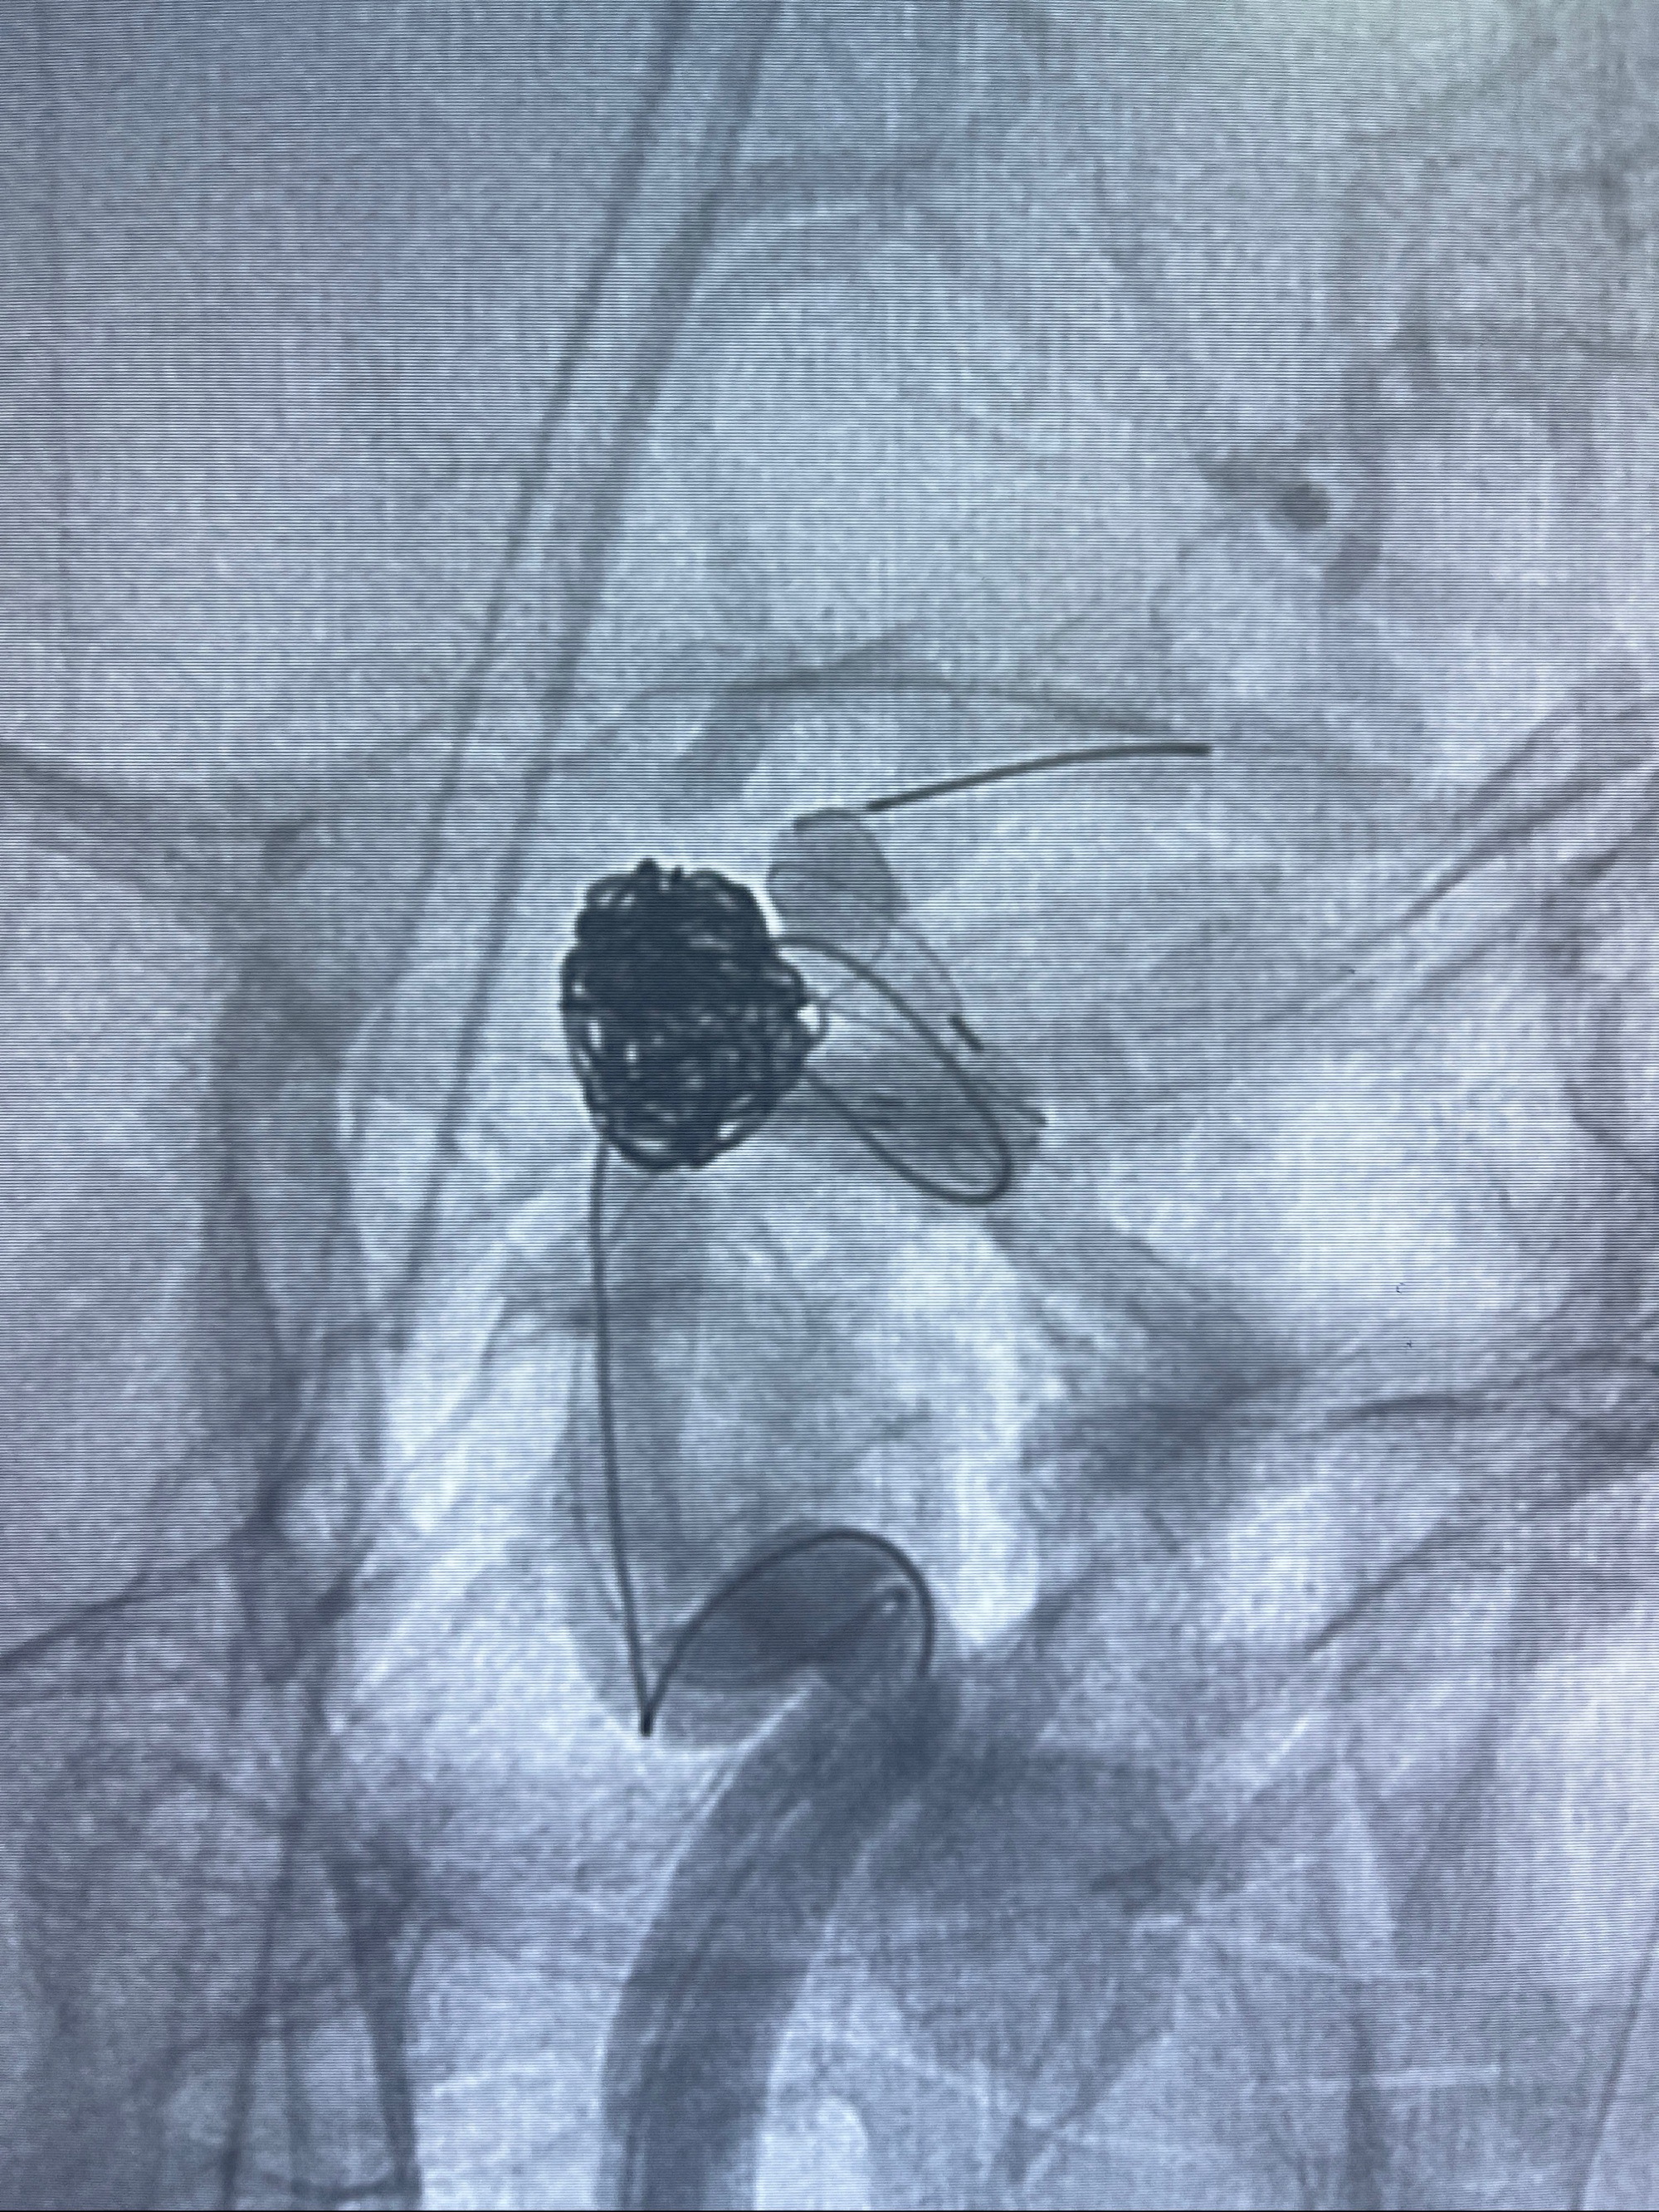

密网支架辅助栓塞

- Tubridge 4.0-20mm密网支架

- 加奇微弹簧圈:7*30/6*20/5*20/2*8

术后3D显示支架贴壁佳